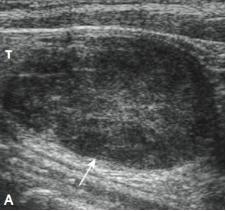

• *Hypoechoic solid lesion**

• Homogeneous

• Oval (~1cm)

• *Hypervascular**

• Arch

• Feeding vessel

• Differentials:*

• Lymph node*

• Thyroid nodule*